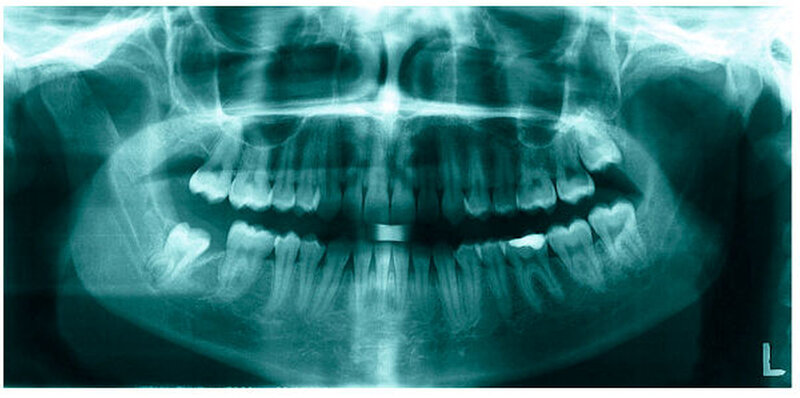

Bereits 2004 wies Carla Evans [Evans, 2005] auf das Risikomanagement bei Allgemeinerkrankungen hin und stellte am Beispiel der JIA dar, dass Unterkieferrücklagen und frontal offene Bisse aus der Kiefergelenkzerstörung entstehen können. Die Röntgenaufnahmen einer JIA-Patientin mit oligoartikulärer Form und Beteiligung des rechten Kiefergelenkes zeigen den typischen Verlauf sehr gut. Bei ursprünglich sehr dezenten Befunden, wie einer s-förmigen Mundöffnung von 44 mm, einer geringen Mittenabweichung um 2 mm nach rechts und einem frontal offenem Biss klagte sie über Schmerzen beim Essen, was den Anlass zur weiteren Diagnostik bot. Die erste Panoramaröntgenschichtaufnahme (Abbildung 1a-c) zeigt auf der rechten Seite einen abgeflachten Kondylus und eine bereits verstrichene Fossa condylaris. Ein Jahr später vermittelt das Fernröntgenseitenbild (Abbildung 1d) trotz fortschreitender kondylärer Resorption ein harmonisches Bild, während nach drei Jahren bei voranschreitendem Abbau des rechten Kondylus (Abbildung 1e) eine Rücklage der Mandibula und eine Bissöffnung manifest sind (Abbildung 1f).

Mithilfe der Panoramaröntgenschichtaufnahme lässt sich in bis zu 67 Prozent der Fälle bereits eine Kiefergelenkdestruktion bei Kindern mit JIA feststellen [Küseler et al., 1998; Twilt et al., 2004; Abramowicz et al., 2014]. Eigene Untersuchungen bestätigten die Eignung als Screening-Verfahren [Mäckelmann, 2008].

Bei 152 durchschnittlich 12-jährigen Rheumapatienten wurden die kondyläre Morphologie und Symmetrie beziehungsweise Asymmetrie im Vergleich zu einer Kontrollgruppe anhand der OPG analysiert. Zur Analyse erfolgte die Zuordnung zu vier morphologischen Graden je Kondylus (Abbildung 3a-d). Bei 45 Prozent der Rheumapatienten waren morphologische Veränderungen im Rahmen kondylärer Resorption unterschiedlicher Ausprägung zu finden. Die „Kontrollpatienten“ ohne JIA zeigten nur zu 14 Prozent formatypische Kondylen. Der Unterschied zwischen den beiden Gruppen war signifikant. Daher sollte bei der Routineauswertung von Panoramaröntgenschichtaufnahmen auf diese Anzeichen geachtet werden, insbesondere auch unter dem Aspekt, dass laut Assaf [2011] durchschnittlich 4,3 Jahre zwischen Erstmanifestation der JIA und Erstvorstellung in der Rheumasprechstunde des UKE liegen.